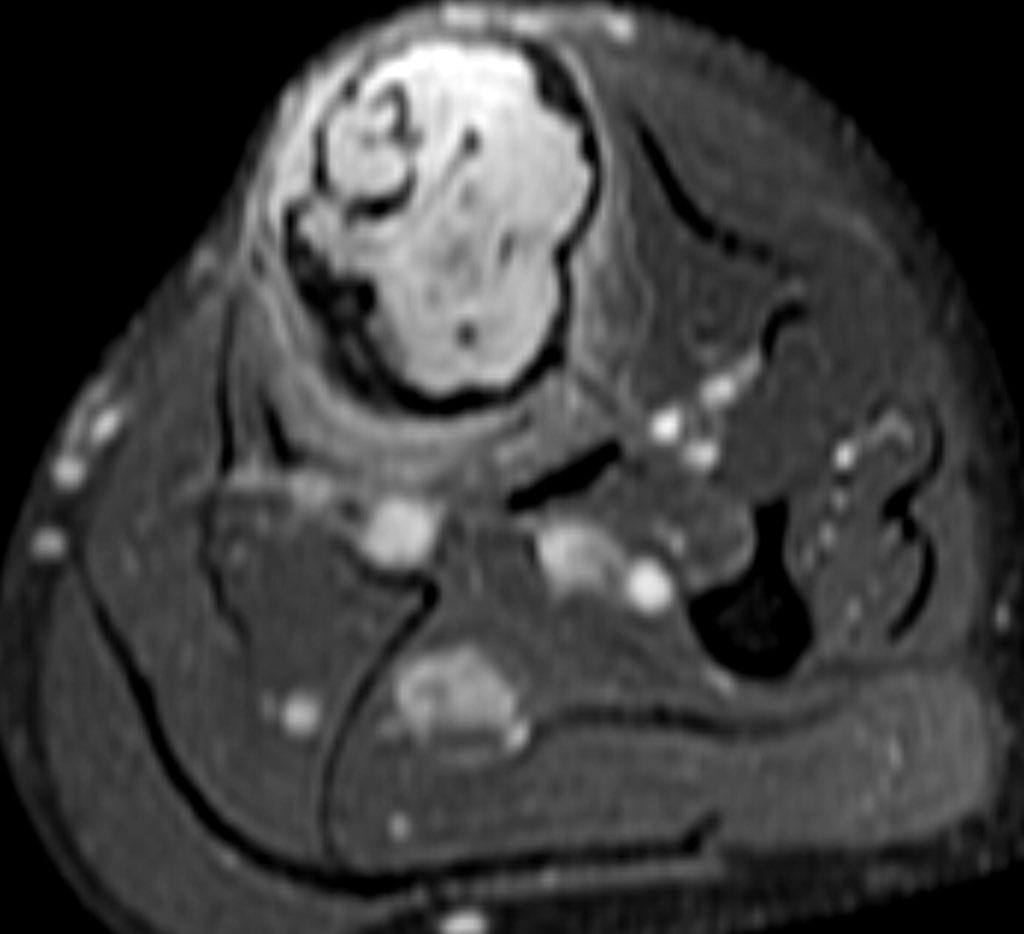

MRI is mandatory for accurate local staging (intramedullary extent, multifocal tibial and fibular disease and extra-osseous extension) and surgical planning. AD is typically isointense / mildly hyperintense to muscle on T1 weighted images

similar to fat on fast spin-echo T2 and hyperintense on inversion recovery and fluid-sensitive fat saturated sequences. The tumour enhances intensely and homogeneously.

The tumour in the current case appeared to have arisen in the anterior cortex, extending inferiorly into both cortex and medulla, as a single focus of disease. The trabeculated appearance on radiographs appears to reflect the unusual extension of tumour through tibial cortex.

, with preservation of vertical ridges of cortical bone, surrounded by tumour, adjacent to areas of marked cortical thinning. Oedema-like hyperintensity on the bone surface suggests imminent fracture